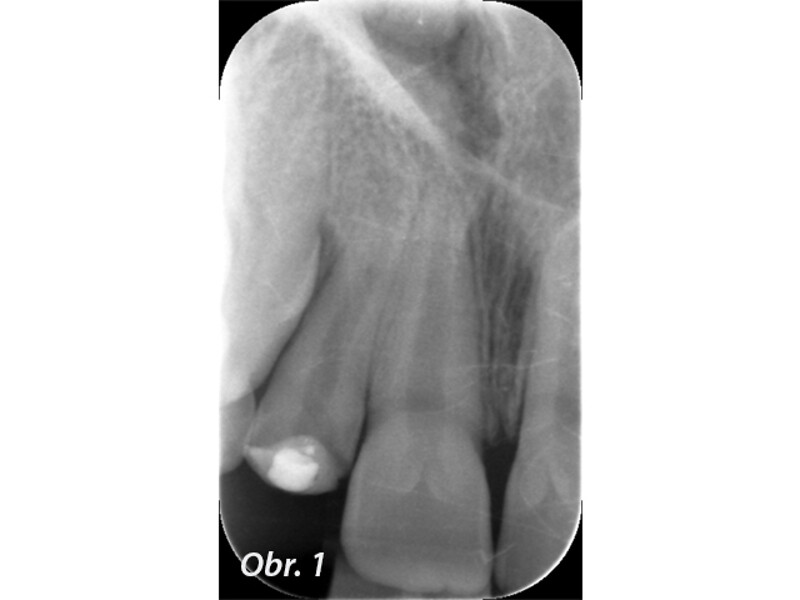

Indikační šíře MTA: Soubor kazuistik